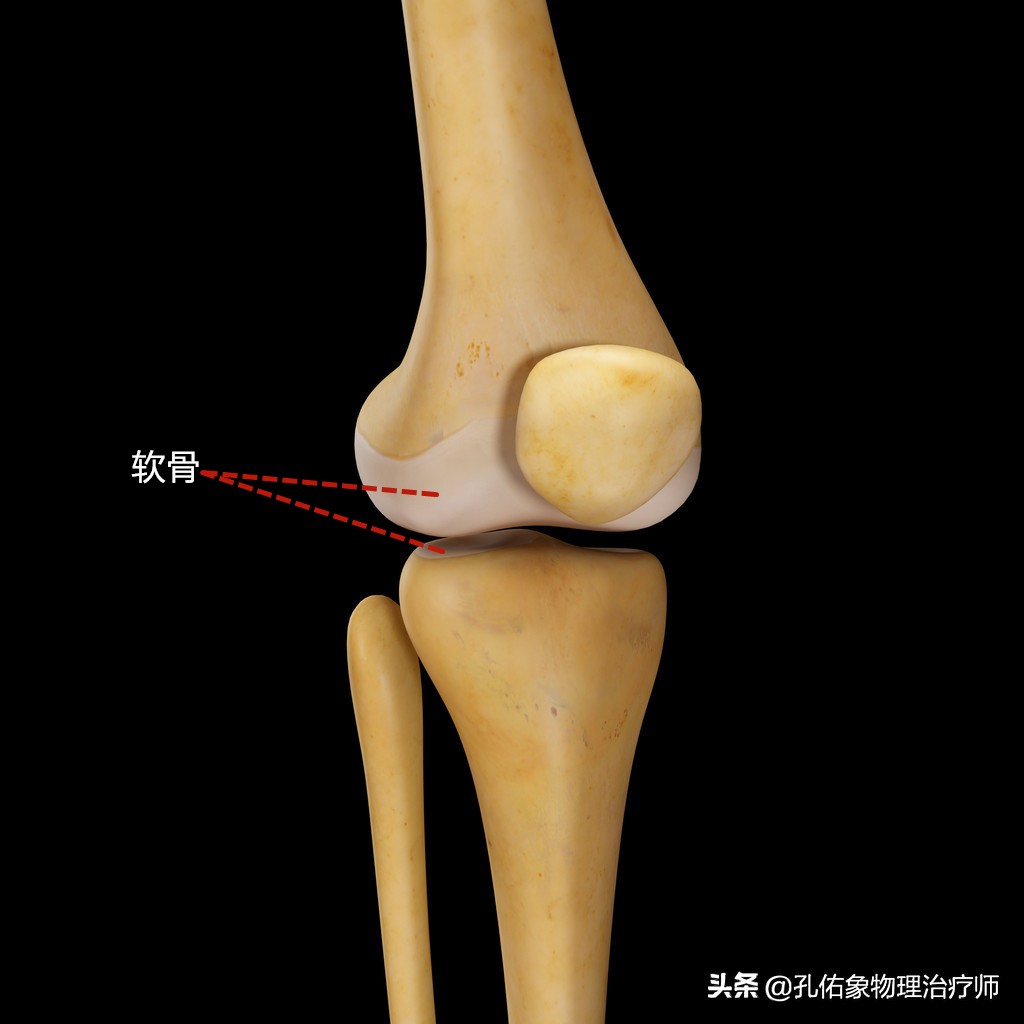

在正常人体膝关节中,大腿骨和小腿骨及膝盖骨的连接处关节面,还有一种很重要的结构,如下图所示的灰白色物质,就是软骨。

软骨

我们在正常活动屈伸小腿的时候,膝关节内健康正常的软骨面之间就可以很顺畅的滑动,并且能够缓冲身体在活动时(如走路,上下楼,跑步,下蹲-起立)产生的局部压力。在正常情况下,膝关节内的软骨摩擦力是非常小的,一般正常的活动是不会造成软骨磨损的。

但凡你过度使用膝关节,或是腿型及姿势的异常,使膝关节不恰当的受力,就会导致关节面上的软骨发生磨损,软骨下面的骨质就会在膝关节活动屈伸小腿时相互接触摩擦而导致疼痛,从而影响膝关节内部的滑膜增生,导致关节的积液肿胀。这种问题就是我今天要着重介绍的髌骨软骨软化,不知你听说过没?了解过没?